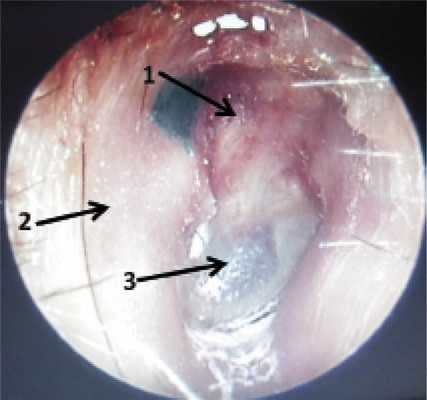

Рис. 1. Правое ухо. Отоэндоскопия отоскопом прямого видения 00 фирмы KARL STORZ. 1 — облитерированный эпитимпанум, 2 — задняя стенка наружного слухового прохода после полной мастоидопластики, 3 — неотимпанальный лоскут.